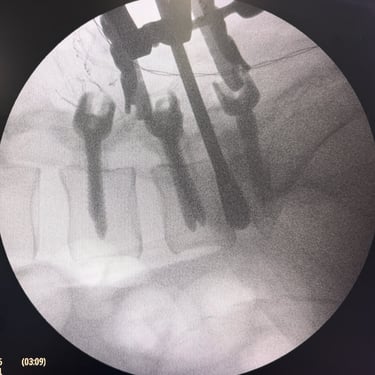

Manejo quirúrgico de la hernia lumbar con inestabilidad: enfoque moderno con FTP y TLIF

La hernia lumbar con inestabilidad vertebral es una patología frecuente que causa dolor lumbar persistente, ciática y limitación funcional, afectando la calidad de vida del paciente. Cuando el tratamiento conservador no logra resultados adecuados, la cirugía se convierte en la mejor opción terapéutica. La fijación transpedicular con tornillos (FTP) junto con la técnica TLIF (Transforaminal Lumbar Interbody Fusion) permite estabilizar la columna, descomprimir las estructuras nerviosas y lograr una adecuada fusión ósea. Este abordaje, especialmente mediante técnicas mínimamente invasivas (MISS), ofrece múltiples beneficios, como menor daño muscular, menor dolor postoperatorio y recuperación más rápida, facilitando el retorno temprano a las actividades cotidianas con mejores resultados clínicos.